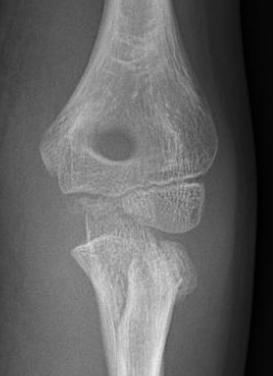

Xray

Displaced and angulated radial neck fracture